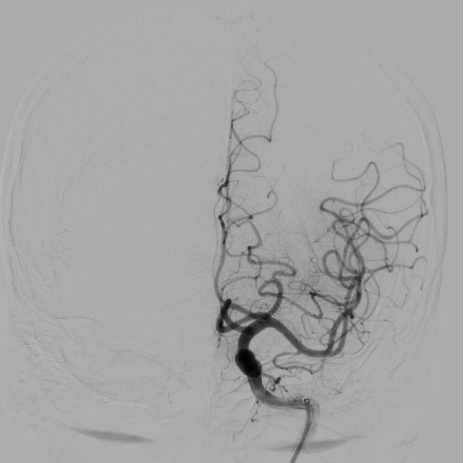

术中脑血管造影证实责任血管为左侧大脑中动脉M2上干闭塞。M2段血管取栓治疗属于MeVO取栓。

术中,介入医生凭借丰富的临床经验与精准的操作技巧,在纤细迂曲的血管通道中谨慎操控器械,逐步推进至血栓位置,最终成功将M2上干内的血栓取出,实现血管再通。

(患者术后血管血流恢复)

术后刘先生的语言功能立即恢复。经专业术后护理,第三天他的语言、肢体活动完全正常,各项指标稳定。目前,刘先生已康复出院,回归正常生活。